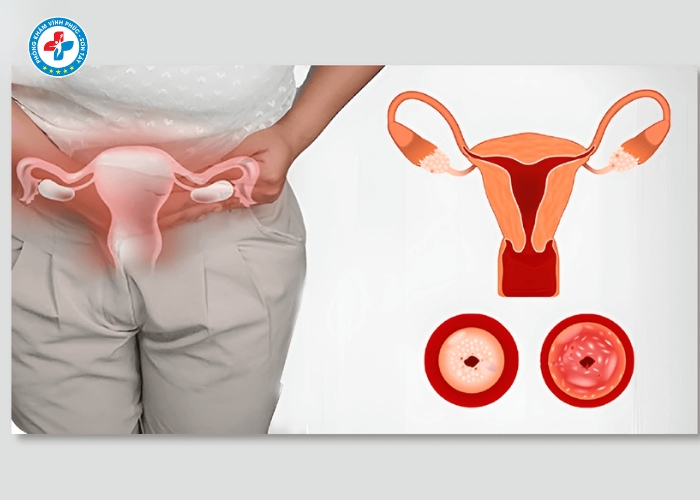

Dấu hiệu nhận biết lộ tuyến cổ tử cung

Các biểu hiện thường gặp:

- Khí hư ra nhiều, có mùi hôi

- Khí hư màu trắng đục, vàng hoặc xanh

- Ngứa rát vùng kín

- Đau khi quan hệ

- Xuất huyết nhẹ sau quan hệ

Nếu gặp các dấu hiệu này, chị em nên đi khám sớm.